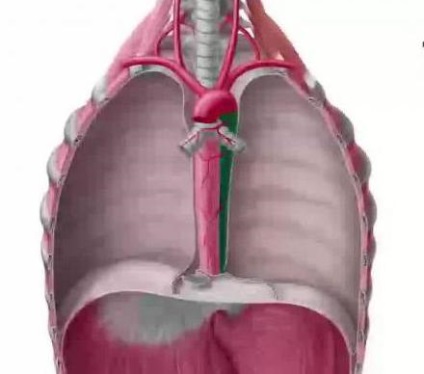

Az ágak a mellkasi aorta

Ez a szegmens, mint már említettük, részét képezi a leszálló aortát. Nem található a hátsó mediastinum, áthalad a gerincoszlopot.

- A hörgő ágak (2-4 db). Kezdve az elülső fal az aorta a régióban egy ága a bordaközi artériák harmadik. Bevitele a kapuk mindkét tüdő, intrabronchiális képződött artériás hálózati ellátó a hörgőket, kötőszövet-képződés (keret) a tüdő, a nyelőcső, a szívburok, a tüdő fal hajók (vénák és artériák). A tüdőszövet hörgő ágak képező anasztomózisok a ágai a pulmonális artériák.

- A nyelőcső ágak (3-4 db). Körülbelül 1,5 din cm, és megszünteti a falakon a nyelőcső (a mellkasi szegmensben). Ezek az ágak indul a mellkasi aorta körüli 4-8 háti csigolyák. Anasztomózisok kialakítva rekeszizom felső, alsó és felső pajzsmirigy, mediasztinális artériák, valamint a bal koszorúér a szív.

- Mediastinalis ágak (mediastinalis) lehet a különböző szállást, mulandó. Gyakran jön részeként szívburok ágak. Vérellátása szál végzett, és a mediasztinális nyirokcsomók hátsó fala (hátsó) pericardium. Forma anastomosisai a fenti ágak.

- Szívburok ágak (1-2 db), vékony és rövid. Aorta ágaznak a homlokfal, a szívburok krovosnabzhaya (háttal). Forma anastomosisokból mediastinalis és a nyelőcső artériákban.

parietális ágak

- Rekeszsérv felső artéria kinyúló aorta vérkeringést végezzük mellhártya és ágyéki szegmens az aorta. United anastomosisokból a rekeszizom alacsonyabb, a belső mellkasi és alsó bordaközi artériák.

- Intercostalis artériák hátsó (10 pár) ágaznak ki az aorta fal és a hátsó, majd 3-11 bordaközi terek. Az utolsó pár alá nyúlik a borda 12 (azaz egy szubkosztális), és belép az anasztomózis lumbális artériás ágak. Az első és a második bordaközben ellátó subclavia. Bordaközi jobb artéria valamivel hosszabb, mint a bal, és menj a tengerparti mellhártya-ig sarkokat, hogy hátul helyezkedik el a hátsó mediastinum, körbeadogatása elülső felületét a csigolyák. A borda feje a bordaközi artériák indulnak hátsó ágai az izmok és a bőr a hát, a gerincvelő (beleértve a köpeny) és a gerinc. A borda szögek artériák között a belső és a bordaközi izmok, meghatározza a parti groove. A artériák a 8. bordaközi tér és alatta alatt fekszenek megfelelő éle, ágaznak oldalsó ágak, hogy az izmok és a bőr az oldalsó részeinek a mellkas, és miután alkotó anasztomózisok a bordaközi elülső ágak a mellkasi (belső) artériát. 4-6 bordaközi artéria ágai, hogy a mell. Intercostalis artériák vérellátását biztosító a mellkas felső részén és alsó három - a rekeszizom és a hasfal (elöl). A harmadik jobb bordaközi artéria küld egy gallyat, hogy jól megy a hörgő és 1-5 x bordaközi artériák kiterjesztése ágak vérrel ellátó bal hörgők. 3-6 th bordaközi artéria ad okot nyelőcső artériákban.